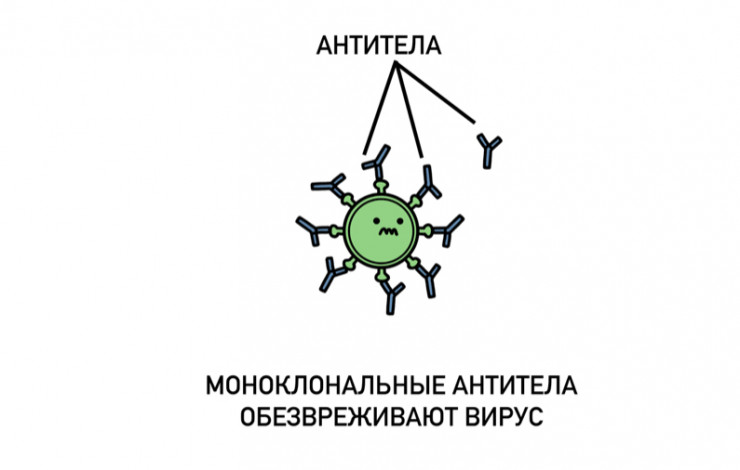

Одно из них – ремдесивир. Этот противовирусный препарат недавно получил одобрение фармацевтического комитета Соединенных Штатов. Также эффективность проявил так называемый коктейль из моноклональных антител. Он как бы заменяет иммунную защиту. Указанные средства недавно испытал на себе американский президент Трамп.